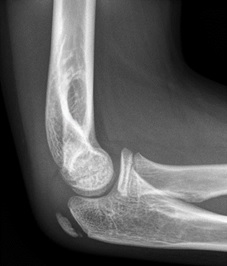

Anterior fat pad seen but NOT elevated, so NOT a joint effusion |

|

Anterior fat pad elevated off anterior surface of humerus = joint effusion |